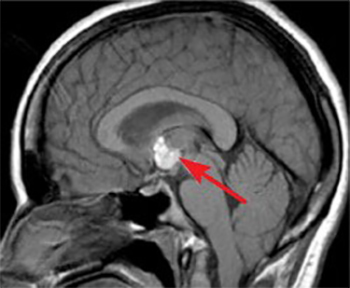

Если личинка цепня попадает в желудок человека, существует высокая вероятность того, что она сможет проникнуть в головной мозг, где может прожить от 5 до 30 лет, в зависимости от иммунитета хозяина. Выделения паразита могут отравить нервную систему, вызвать воспаление головного мозга и даже привести к его отёку.

Признаки инфицирования мозга:

- Постоянные мучительные головные боли.

- Ощущение головокружения и неустойчивости.

- Снижение чувствительности или изменения в ощущениях.

- Затруднения с произношением слов или выражением мыслей.

- Изменения в психическом состоянии или поведении.

- Видения или ощущения чего-то нереального.

- Постепенное ухудшение зрения.

- Состояние уныния или глубокая печаль.

- Эпизоды судорог или необъяснимые припадки.

- Непроизвольное извержение содержимого желудка.

Важное значение имеют данные лабораторных исследований и общая клиническая картина для точного определения диагноза. При цистицеркозе необходимо провести следующие обязательные диагностические процедуры:

- Исследование методом магнитно-резонансной томографии.

- Процедура компьютерной томографии.